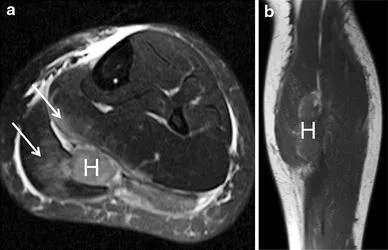

小腿后侧被踢出小腿肌肉挫伤和血肿。横向脂肪抑制T2加权图像显示比目鱼肌和腓肠肌内侧肌腹部沿束的水肿轨迹(箭头)。在两块肌肉之间的筋膜平面形成了血肿(H)。在冠状位T1加权像上,由于内部高铁血红蛋白,亚急性血肿比正常骨骼肌高信号。